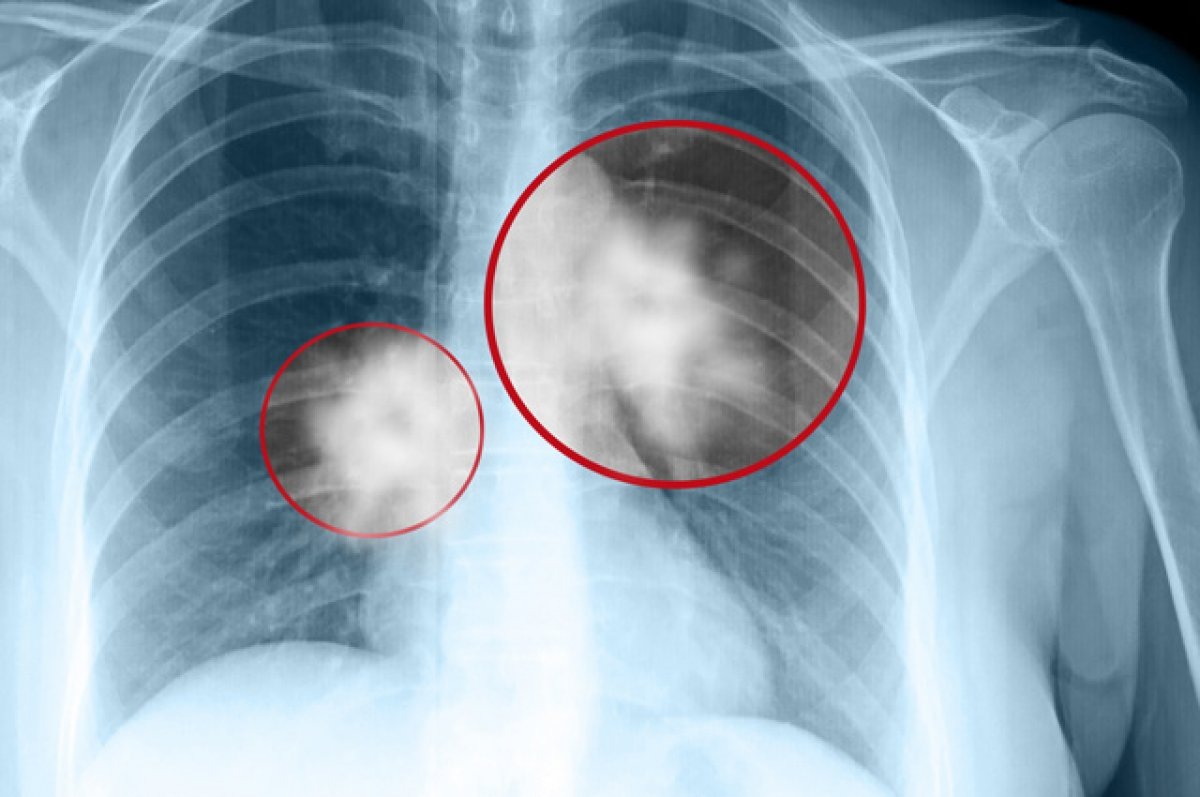

1. Низкодозная КТ лёгких. Золотой стандарт для выявления узлов или опухолей.

2. Рентген грудной клетки. Первичный скрининг, но менее точный.